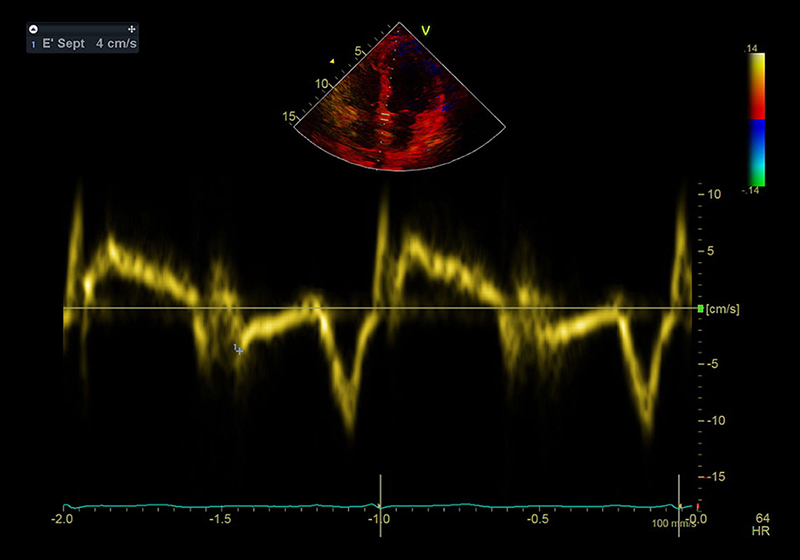

Im Echo beurteilen wir den strukturellen Zustand des Myokards (Herzmuskels), der Herzklappen und des Herzbeutels. Die besondere Domäne der Echokardiographie ist aber die Beurteilung der Funktion von Herzmuskel und Herzklappen. Sie ist damit das wichtigste Instrument zur Diagnostik von Herzinsuffizienz (Herzschwäche) oder Klappenerkrankungen.